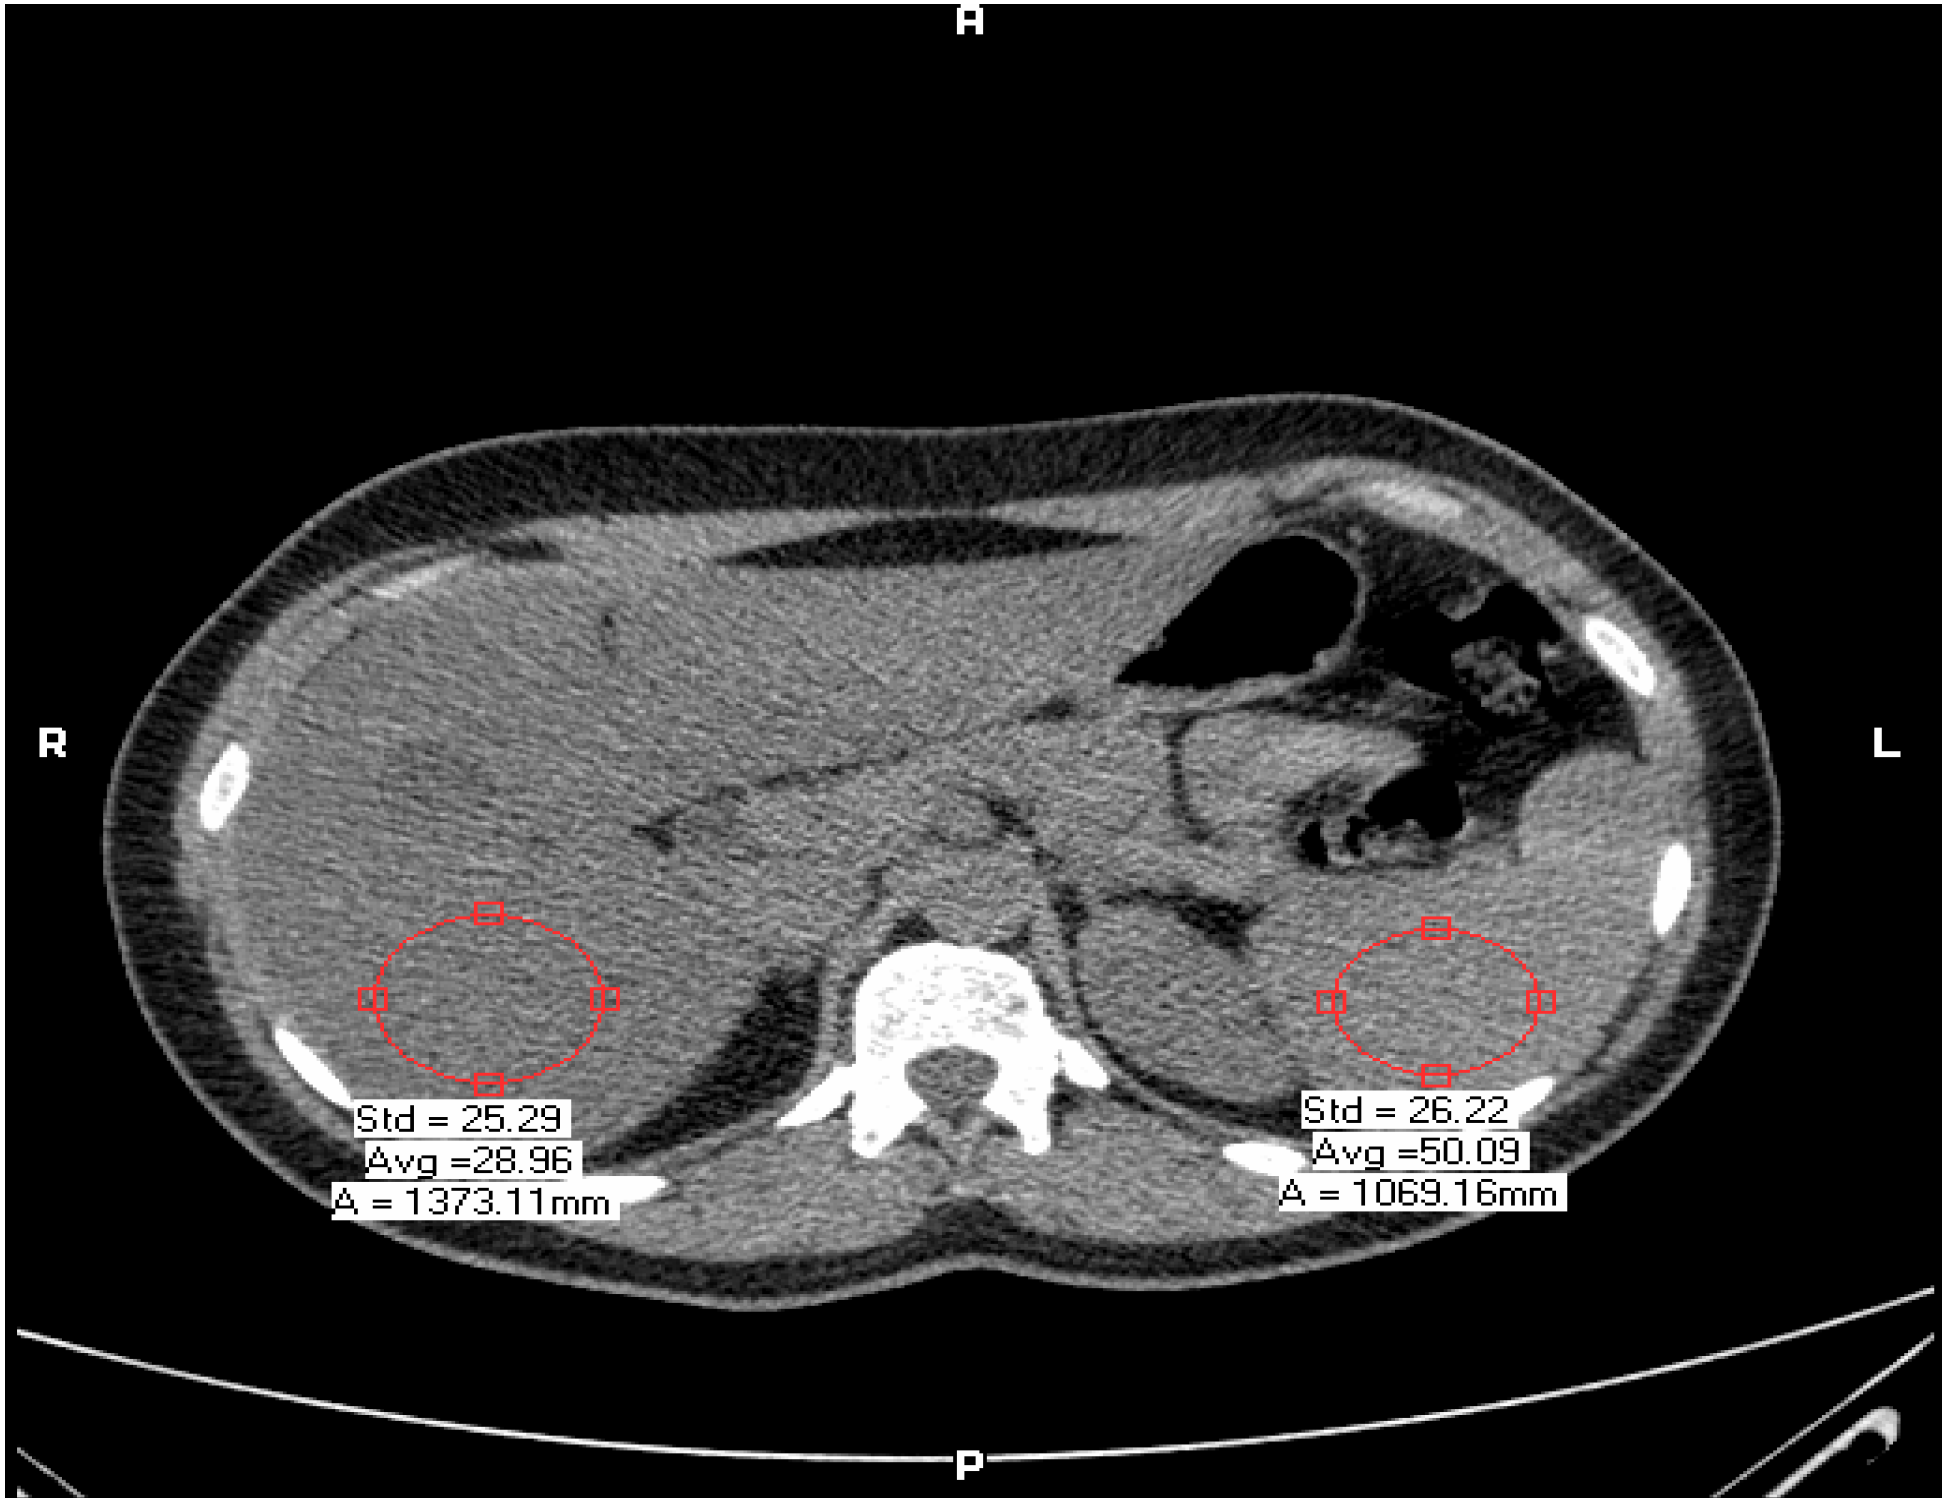

Hepatic steatosis was defined as liver minus spleen density > −10 Hounsfield units by CT [7,28] (Figure 1). All CT examinations were performed by the same experienced radiologist (LA, 20 years experience in radiology) blinded to the clinical status of the patients. The retinal photography procedure followed standardized methods. Briefly, after 5 min of dark adaptation, a 45°, retinalphotograph was taken of one randomly selected eye using an auto focus camera. The photograph was centered on the region of the optic disc and the macula. The photographs were digitized by a high-resolution scanner and the diameters of individual arterioles and venules coursing through a zone located one half to 1 disc diameter from the optic disc margin were measured on the computer bytrained graders who were masked to subject identity. These measurements were summarized as a retinal arteriole-to-venule ratio (AVR). The AVR accounts for magnification differences between photographs; it is characterized by normal distribution in the general population. A smaller AVR indicates narrower arterioles, since venular diameters vary little with blood pressure [20]. Intragraded and intergraded reliability coefficients for repeated AVR measurements were 0.84 and 0.79, respectively. Examples of low and high AVR are shown in Figure 2.

Figure 1.

Example of fatty liver diagnosed by CT: liver minus spleen density > −10 Hounsfield units (HU).

Twenty-nine subjects were diagnosed with NAFLD (without hypertension and without diabetes ) defined by CT (liver minus spleen density ≥ −10 HU), absence of alcohol use (<20 g/day), negative serology for hepatitis B or C diagnosis, negative auto-antibodies, and absence of history of another known liver disease. The control group consisted of 22 gender and age-matched individuals without NAFLD. Intra-observer and inter-observer variability for coronary artery disease (CAD) (stenosis > 50%) was 1% and 5% respectively. Baseline clinical and biochemical characteristics of NAFLD subjects and controls are shown in Table 1. Liver-spleen density was significantly lower in patients with NAFLD than in controls (−15.3 ± 8.9 vs. +6.8 ± 6.7, p < 0.001). The prevalence of smoking was similar among NAFLD patients and controls. Subjects diagnosed with NAFLD had higher triglyceride levels, HOMA values, and waist circumference measurements than controls. All 51 subjects, NAFLD patients and controls, were overweight (BMI 25–30 kg/m2) without statistically significant differences in BMI between the groups (Table 1). Compared with controls, NAFLD patients had a higher percentage of atherosclerotic plaques (70% vs. 30%, p < 0.001), as well as soft plaques (50% vs. 30%, p = 0.001), and greater prevalence of coronary artery disease (30% vs. 15%, p < 0.008), higher right mean IMT, lower retinal artery diameter, and lower AVR (Table 2). After adjustment for possible confounding factors that were identified in univariate analysis, multiple logistic regression analysis demonstrated that NAFLD, IMT, and retinal AVR were strongly associated with CAD, whereas CRP, a biomarker of inflammation was not (Table 3). The association of NAFLD with more severe coronary atherosclerosis remained significant also after adjustment for metabolic syndrome, age, and LDL cholesterol.